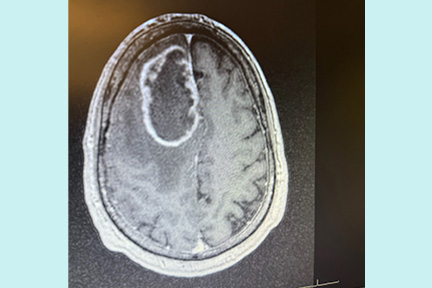

At Memorial Regional Hospital, imaging revealed the cause, a benign brain tumor. Scott describes that moment as surreal. He was confused, exhausted, and unsure what would come next.

View photos from Scott’s journey through treatment and recovery, highlighting moments of strength and resilience.